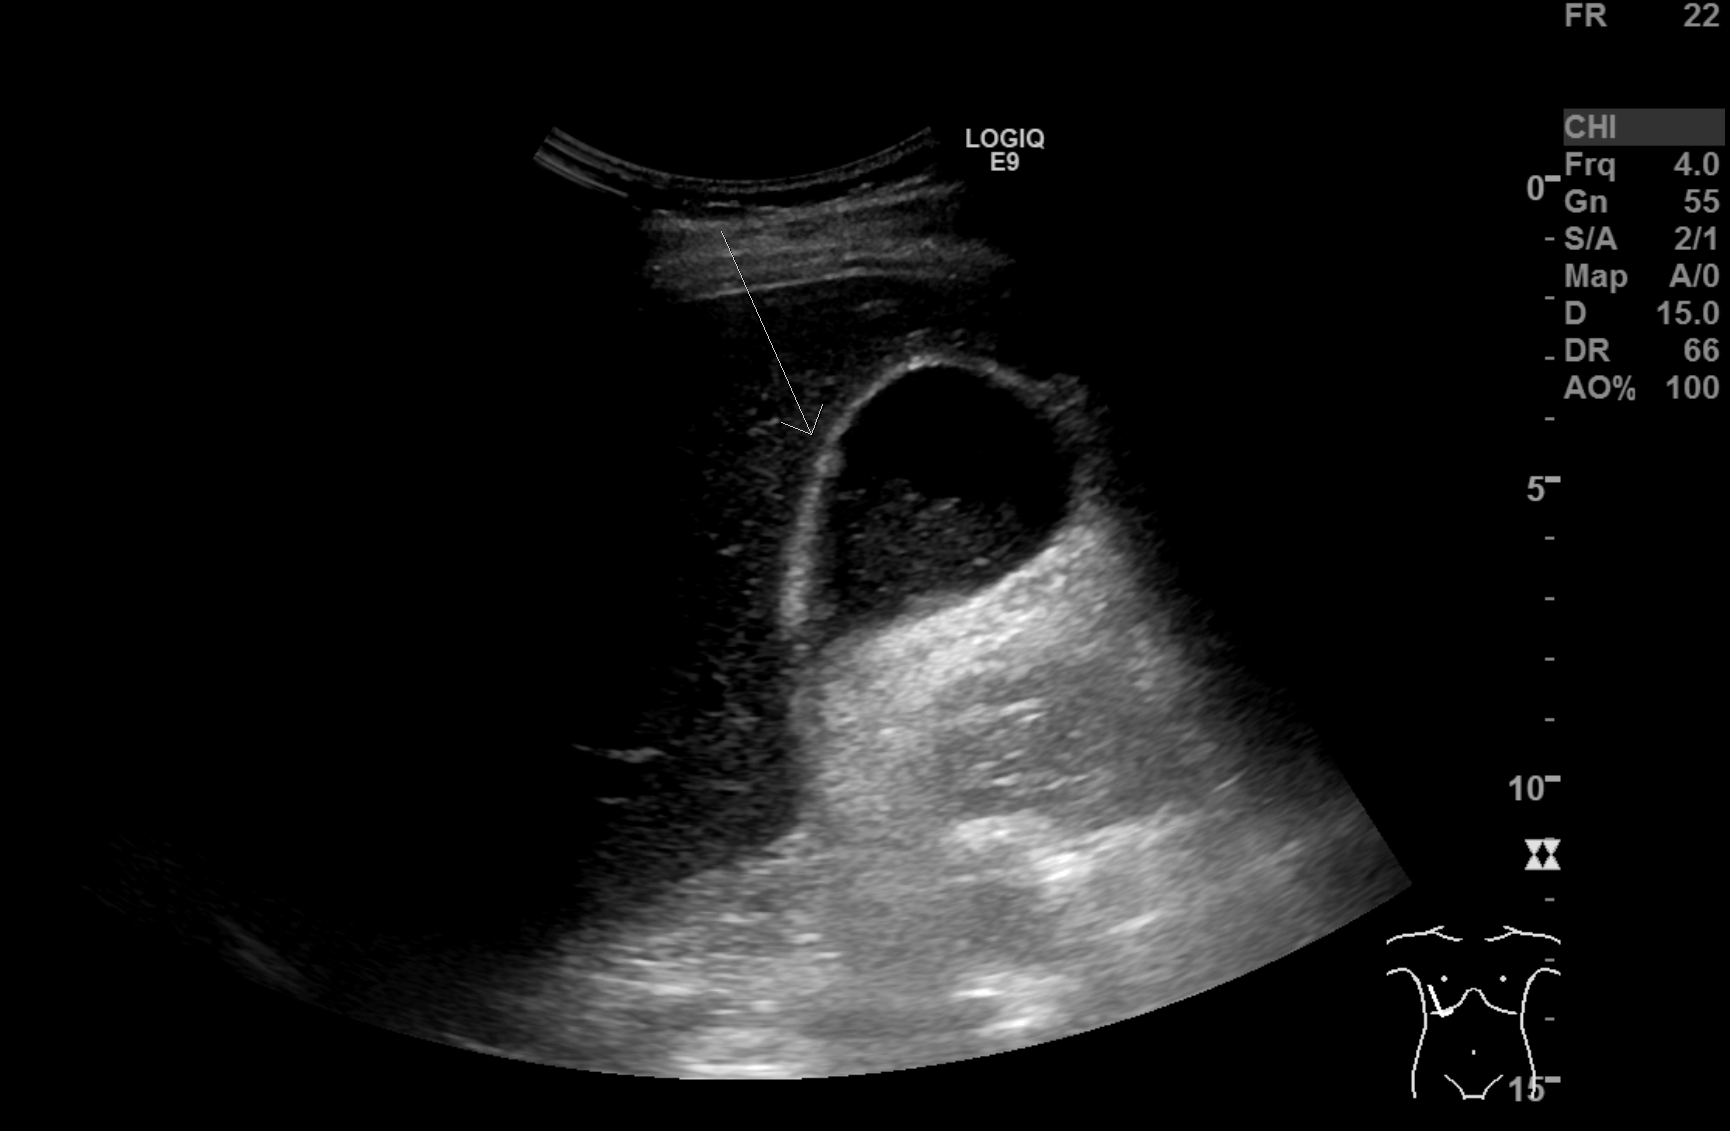

The patient was referred to ultrasound with suspicion of acute cholecystitis as a possible primary diagnosis and acute appendicitis as a secondary possibility. An ultrasound examination of the abdomen was performed using a GE Logiq E9 system with a curved array transducer with a frequency of 1-6 MHz (GE, Chalfont St. Giles). The examination revealed sludge and a stone of approximately 1 cm in the gallbladder. There was no dilatation of the intra- or extrahepatic bile ducts and the gallbladder wall was without thickening (below 3 mm). The other abdominal organs were normal. The appendix could not be seen. Due to the discrepancy between the clinical history, the imaging findings and the planned cardiac surgery the day after, a CT examination was performed to exclude appendicitis. CT showed pericholecystic fat stranding, confirming the diagnosis of cholecystitis. The appendix was located behind the cecum and appeared normal. No other pathology was reported.